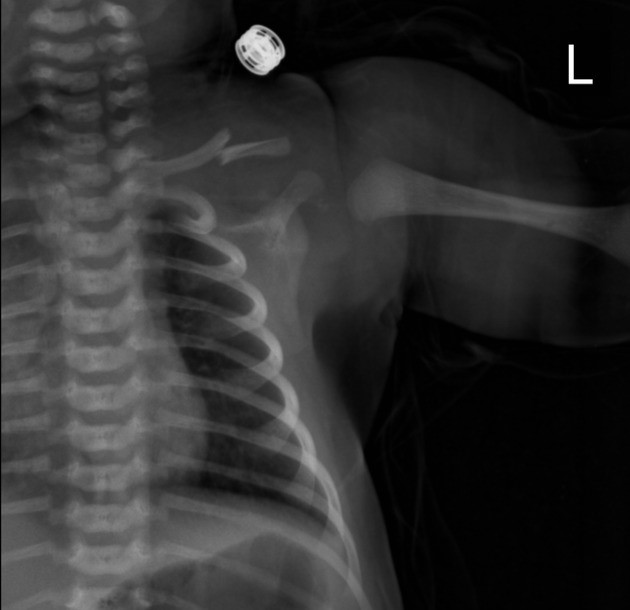

Lưu ý: Ở nhiều trường hợp, trẻ không biểu hiện đau rõ ràng do sơ sinh không nhạy cảm với cảm giác đau như người lớn. Gãy xương đòn thường được phát hiện tình cờ khi trẻ được chụp X-quang ngực thẳng vì một lý do khác.